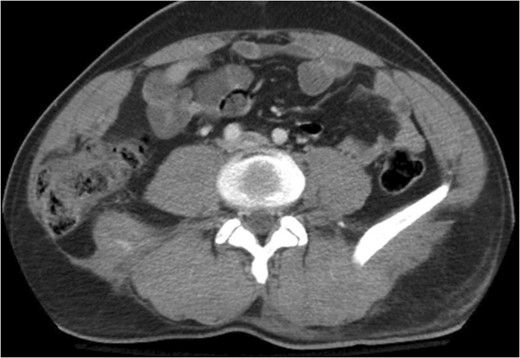

A 43-year-old male patient presented with a right-sided traumatic lumbar hernia after a blunt mechanism. The patient had been pinned between a dirt-mover’s claw arm resulting in a crush mechanism. He sustained injuries to the lumbar spine, sacrum, abdominal wall and 12th rib. On presentation, he did not have clinical or radiographic evidence necessitating abdominal exploration and was observed in a monitored setting. Computed tomography imaging demonstrated a Grynfeltt defect with herniation of the ascending colon and cecum through an area defined by the 12th rib, quadratus lumborum and internal oblique (Figures 1 and 2). After several days of observation and recuperation, the patient continued to have significant pain overlying the hernia site. We electively brought him to the operating room on post-injury Day 4. A laparoscopic repair of the traumatic hernia was performed. Key operative steps included: (i) Wide exposure of the hernia defect via incision of the peritoneum and transversalis as well as mobilization of the ascending colon and duodenal sweep (Figures 3 and 4). (ii) Primary repair of the defect with intra-corporeal suturing of the oblique musculature (Figures 5 and 6). (iii) Placement of an underlay mesh with appropriate redundancy at least 4 cm in all directions around the defect and seating against the iliac crest (Figure 7). Post-operative imaging demonstrates obliteration of the hernia defect and restoration of the abdominal wall (Figures 8 and 9). The patient has recovered, returned to the work force and has no pain or bulge at the repair site 6 months after injury.

Recreation of the abdominal wall contour is seen on the post-operative computed tomography.